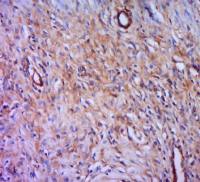

| 产品图片 |  Sample: BV2 Cell (Mouse) Lysate at 40 ug Primary: Anti- CXCL16 (bs-1441R) at 1/300 dilution Secondary: IRDye800CW Goat Anti-Rabbit IgG at 1/20000 dilution Predicted band size: 27 kD Observed band size: 27 kD  Tissue/cell: human lung carcinoma; 4% Paraformaldehyde-fixed and paraffin-embedded; Antigen retrieval: citrate buffer ( 0.01M, pH 6.0 ), Boiling bathing for 15min; Block endogenous peroxidase by 3% Hydrogen peroxide for 30min; Blocking buffer (normal goat serum,C-0005) at 37℃ for 20 min; Incubation: Anti-CXCL16 Polyclonal Antibody, Unconjugated(bs-1441R) 1:200, overnight at 4°C, followed by conjugation to the secondary antibody(SP-0023) and DAB(C-0010) staining  Images kindly provided by Dr. Denny Cottle from the publication, Fetal inhibition of inflammation improves disease phenotypes in Harlequin Ichthyosis.Formalin-fixed and paraffin embedded mouse skin probed with Rabbit Anti-CXCL16 Polyclonal Antibody (bs-1441R) at 1:50 for two hours at room temperature (green channel).  Paraformaldehyde-fixed, paraffin embedded (Rat colon); Antigen retrieval by boiling in sodium citrate buffer (pH6.0) for 15min; Block endogenous peroxidase by 3% hydrogen peroxide for 20 minutes; Blocking buffer (normal goat serum) at 37°C for 30min; Incubation: Anti-CXCL16 Antibody, conjugated (bs-1441R-AF488) at 1:100 overnight at 4°C; DAPI (5ug/ml, blue, C-0033) was used to stain the cell nuclei.  Blank control: A431. Primary Antibody (green line): Rabbit Anti-CXCL16 antibody (bs-1441R) Dilution: 3μg /10^6 cells; Isotype Control Antibody (orange line): Rabbit IgG . Secondary Antibody: Goat anti-rabbit IgG-AF647 Dilution: 3μg /test. Protocol The cells were incubated in 5%BSA to block non-specific protein-protein interactions for 30 min at at room temperature .Cells stained with Primary Antibody for 30 min at room temperature. The secondary antibody used for 40 min at room temperature. Acquisition of 20,000 events was performed. |